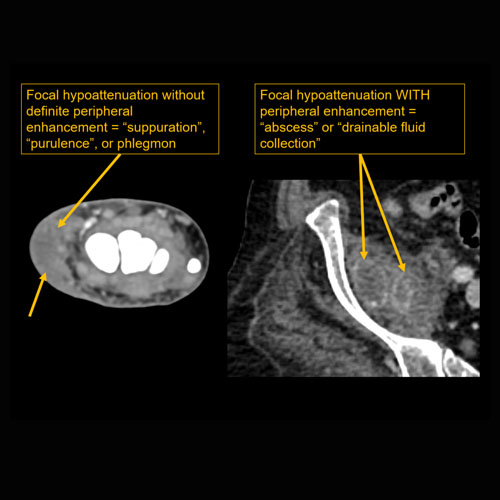

There is confluent hypoenhancement to suggest phlegmon, suppuration, abscess, or drainable fluid collection. |

No | NA |